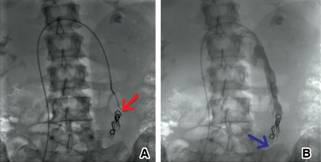

Se llevó a la mujer a la sala de hemodinamia; bajo anestesia general, se llevó a cabo punción de ambas venas femorales y se colocaron introductores 6 Fr. A través del acceso derecho, se canuló la vena cava inferior; posteriormente, la vena renal izquierda (Figura 2A). Se realizó un disparo con medio de contraste y se descartó causa oclusiva. Se visualizó la vena gonadal izquierda dilatada (Figura 2B). Con posición de Trendelemburg modificada, se observó importante reflujo y presencia de venas colaterales dilatadas en la pelvis (Figura 2 C y D). Se canuló, de igual manera, la vena hipogástrica derecha con técnica de paso de guía contralateral a través del acceso izquierdo y se observaron abundantes colaterales y reflujo venoso. Se decidió realizar embolización selectiva con oclusores espirales, con desaparición evidente de las venas colaterales (Figuras 3 y 4).

Figura 4: Canulación selectiva de la vena hipogástrica derecha ( A. Flecha roja), se observan múltiples venas colaterales ( A y B Flechas azules). Embolización selectiva con dispositivo de cierre en espiral del tronco venoso principal ( C. Flecha roja), desaparición de venas colaterales ( C. Flecha azul).